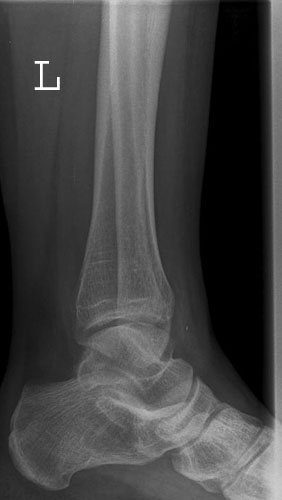

Sprunggelenk

OSG a.p.

Fehler

Außenrotation bzw ungenügende Rotation des Fußes nach innen. Der mediale Gelenkspalt projiziert sich besonders schön frei, hingegegen ist der laterale Spalt verschattet.

Abhilfe

Fuß weiter nach innen drehen lassen, bis beide Malleolen auf einer Höhe parallel zum Film stehen.